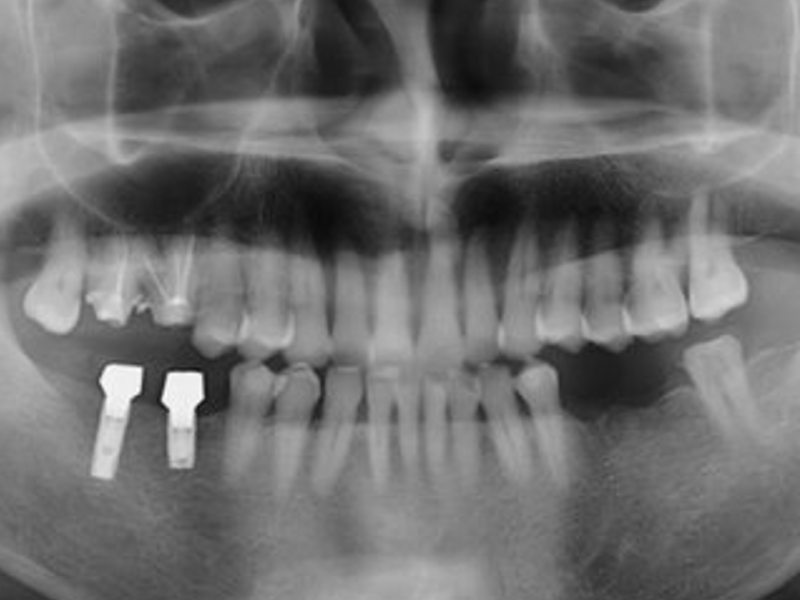

1. Diagnóstico y Planificación:

- Evaluar la salud bucal y de encías del paciente.

- Utilice rayos X o tomografías computarizadas para evaluar la mandíbula y las estructuras circundantes, determinando la ubicación adecuada para la colocación del implante.

- Si la encía y el hueso son lo suficientemente fuertes, programe la cirugía; de lo contrario, es posible que se requiera una cirugía de injerto óseo, cuya fusión tardará unos seis meses.